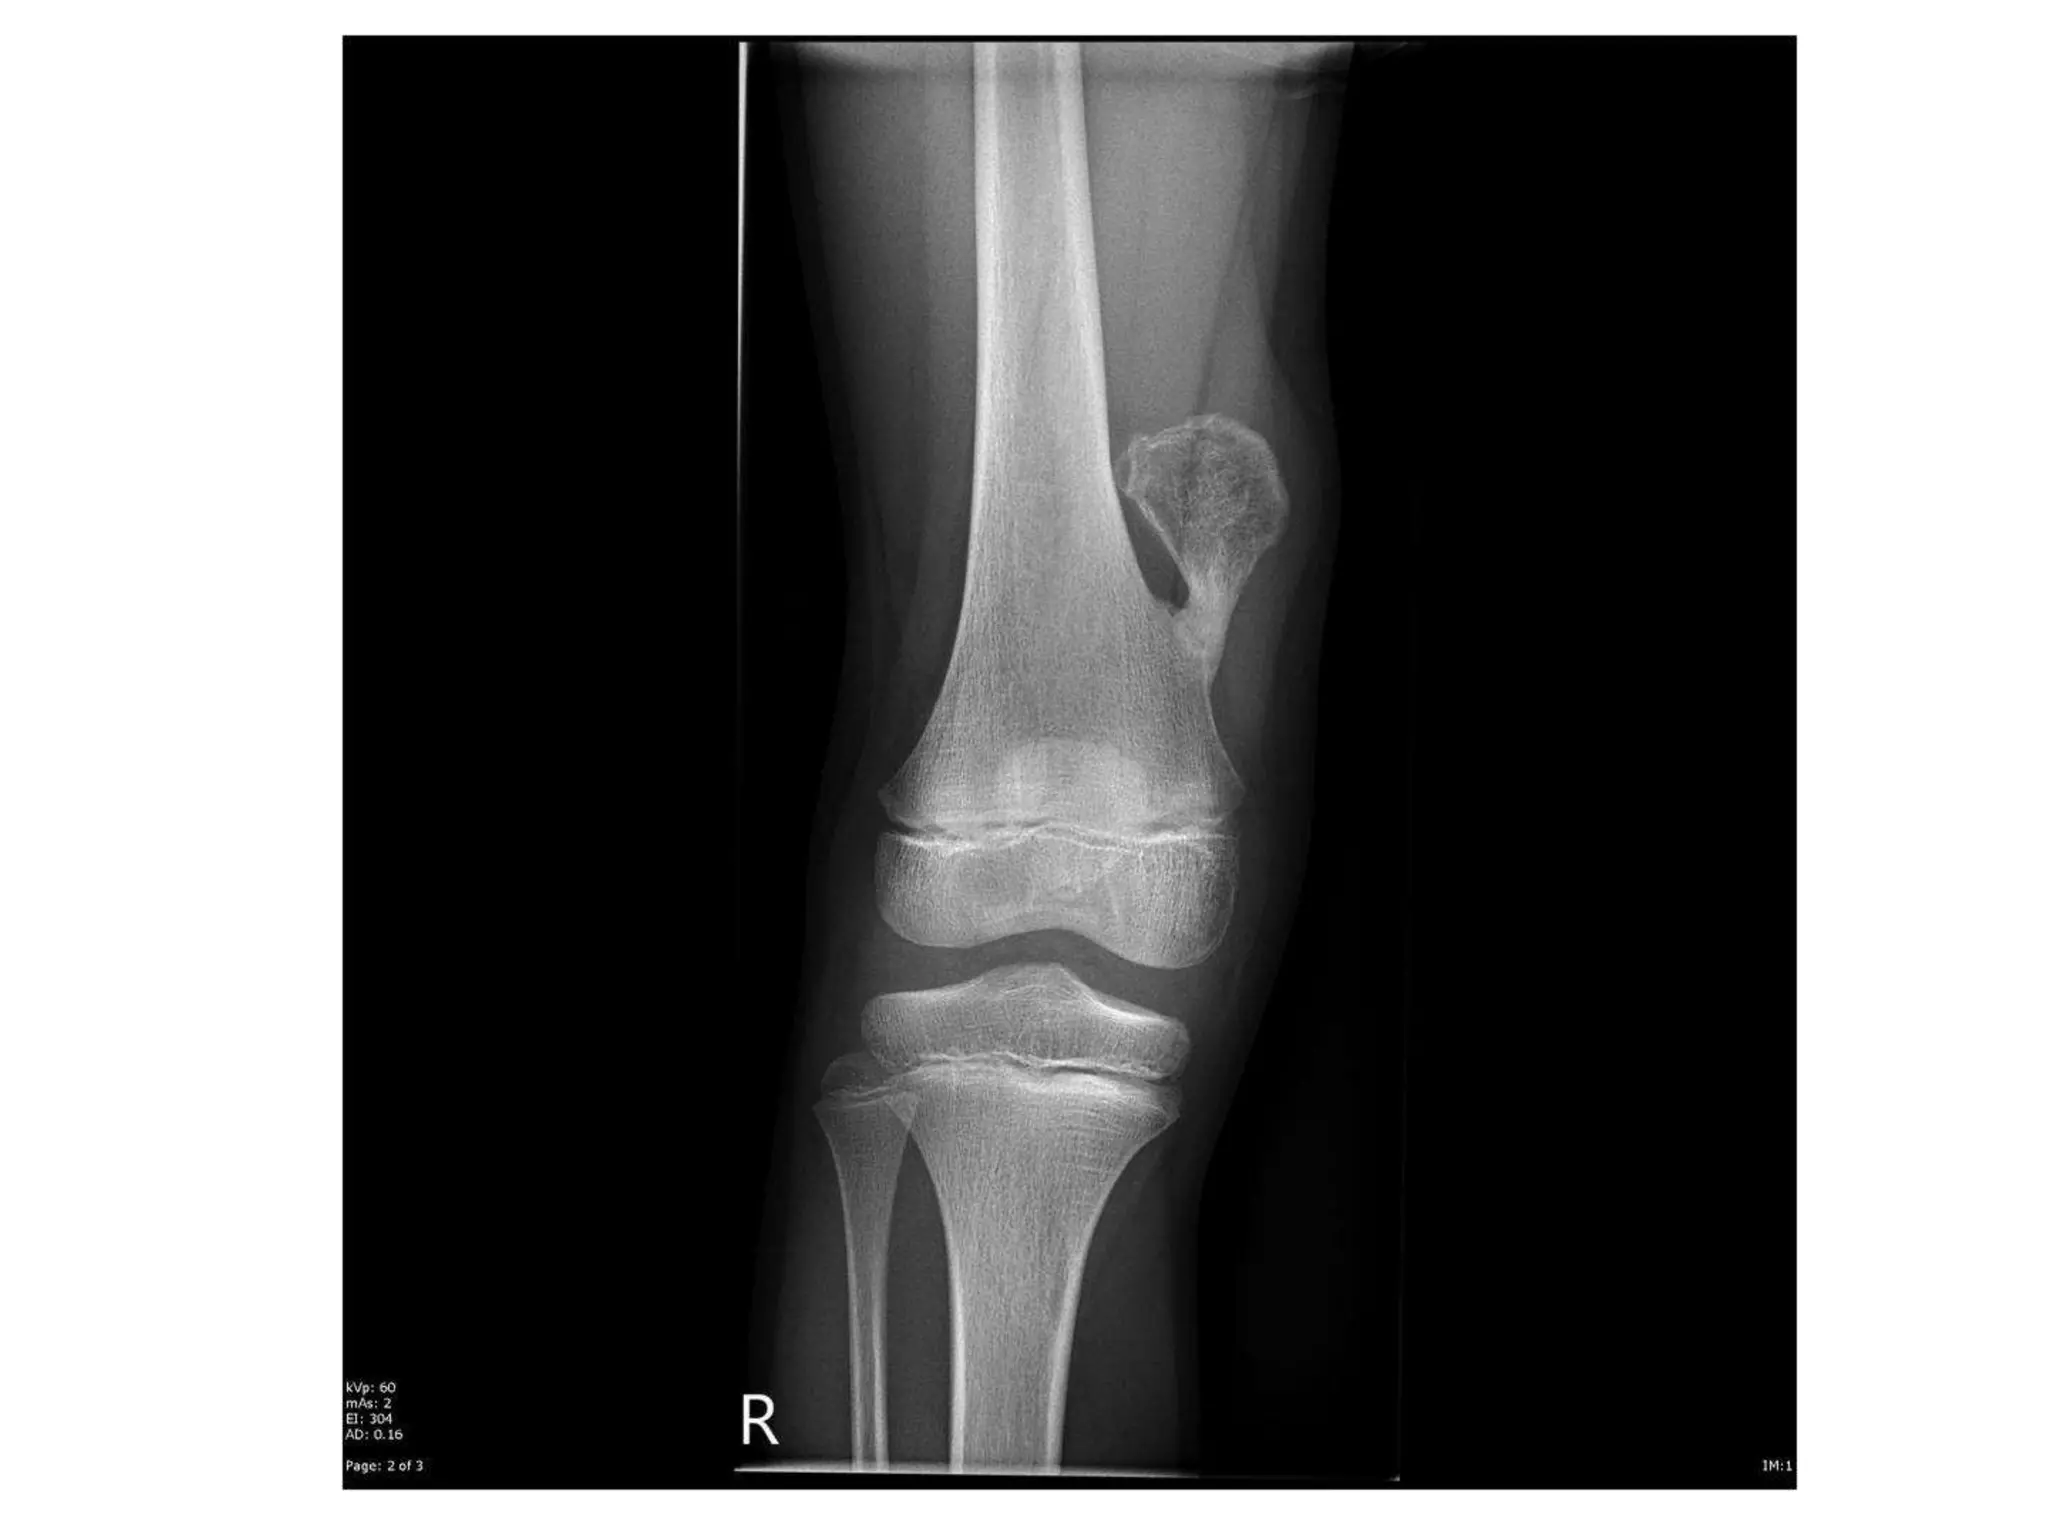

CASE SCENARIO

• A 32 year-old lady presents with slowly-growing

swelling over the upper part of her left tibia since

5 months.

• There has been increasing discomfort and pain

over the last few weeks.

• There are no constitutional symptoms but she

also has noticed swelling in her left knee since

few days.

• On examination there is a diffuse bony swelling

over the proximal tibia with areas of crepitus in

between. She also has patellar tap test positive.

INVESTIGATIONS

• X-ray of the affected bone

A solitary radiolucent lytic lesion

Eccentrically located at the epiphyseal end of long bone

Bounded by subchondral bone plate

Centre showing soap-bubble appearance due to ridging of

the surrounding bone (homogenously lytic with trabecular

of the remnants of bone traversing it, hence giving a

loculated appearance)

Expansion or ballooning of overlying cortex

Thinning out of the overlying cortex, probably perforated at

places

No calcification within tumor, no reactive sclerosis around

the tumor and no invasion of the adjacent joint